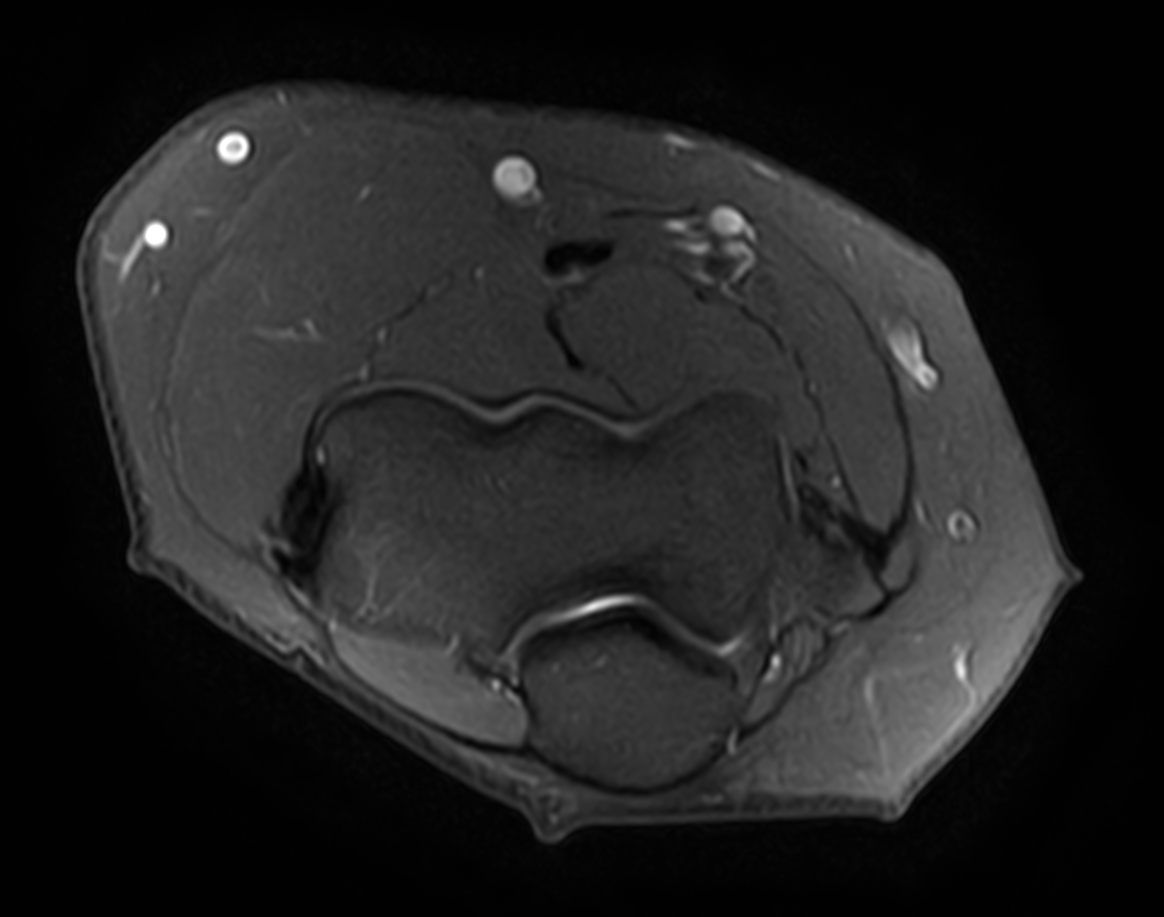

Axial PDw SPAIR